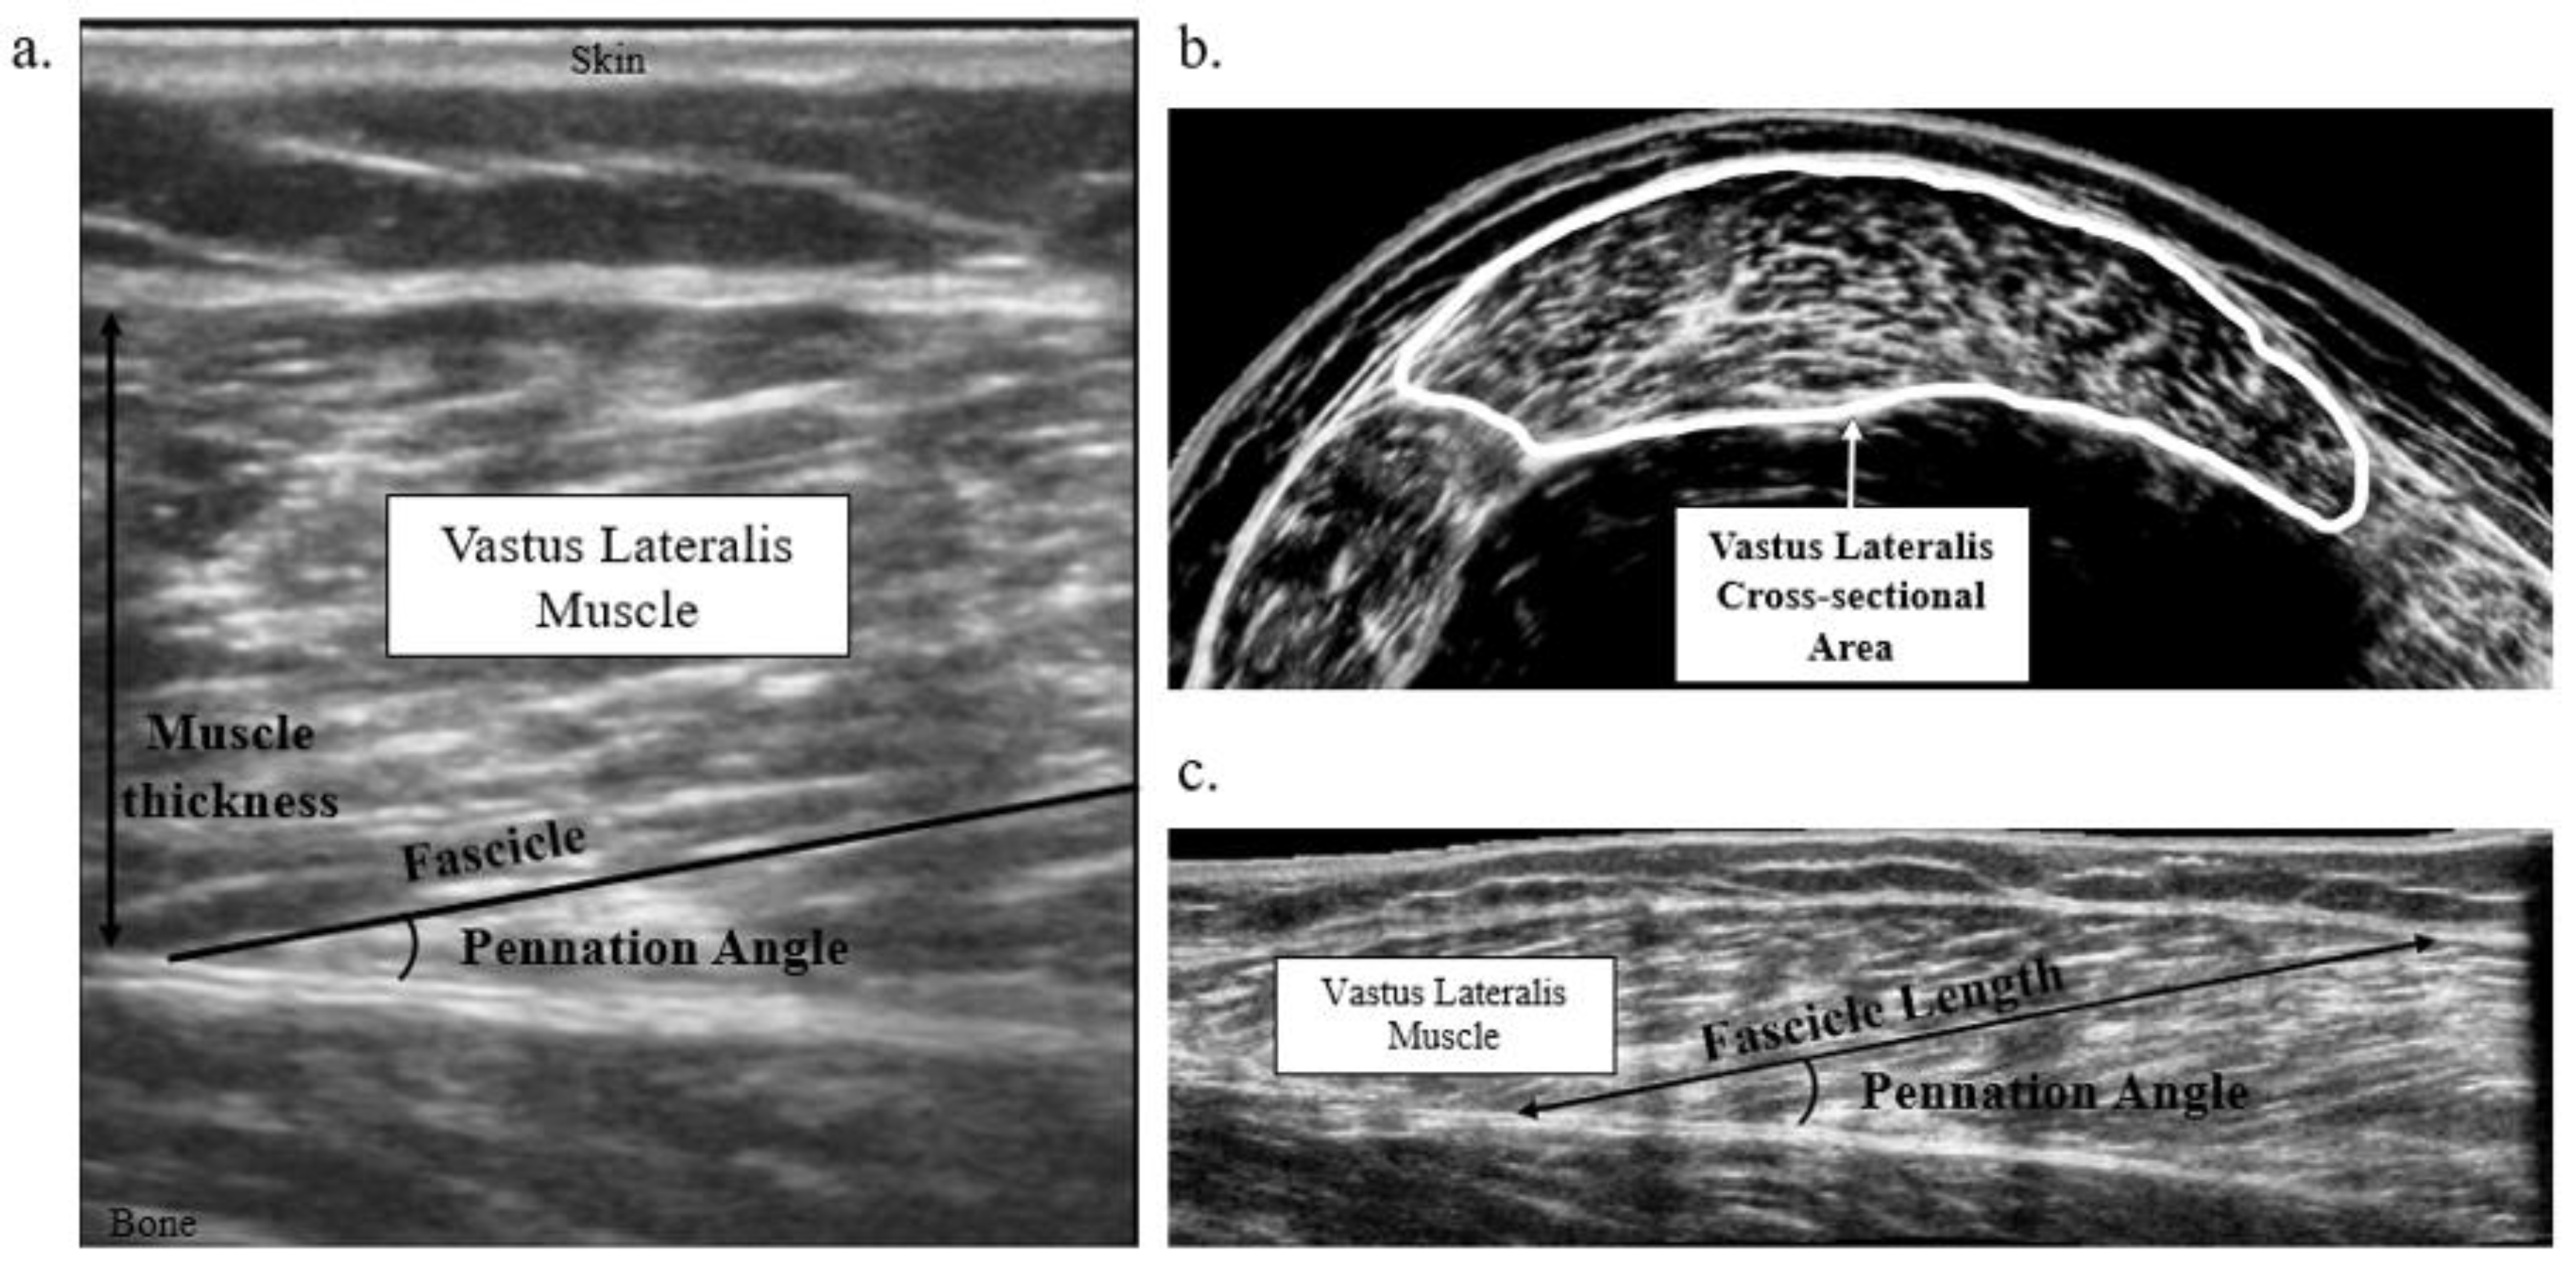

2.2. Muscle Macrostructure